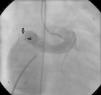

The patient was referred for a diagnostic cardiac catheterization. Angiography confirmed a coronary fistula measuring 13 mm in diameter at the aortic end and draining into the right atrium (RA) through at least two small openings (Figure 1). The left anterior descending (LAD) and circumflex (Cx) arteries originated in the proximal extremity of the fistula through two separate orifices. Catheterization showed normal right and left heart pressures, oxygen saturation step-up in the right atrium and Qp:Qs of 1.7. Informed consent was obtained and percutaneous closure of the fistula was attempted using a 16 mm Amplatzer® vascular plug II (AGA Medical). Through a femoral approach, a 7 Fr venous and a 6 Fr arterial sheath were used. A 6 Fr Concierge Amplatz Left 2 guiding catheter was positioned in the aorta at the fistula entrance and a 0.035 in Terumo® hydrophilic guide wire was advanced along the fistula, until the right atrium was reached. The wire was then snared and an arteriovenous (AV) loop was created. A 7 Fr Amplatzer Delivery System was used to deploy the device through the atrial end (Figure 2). A significant residual shunt was observed after deployment of the device. Cardiac enzymes were within normal range and the ECG showed no abnormalities. After this procedure anticoagulation was prescribed for six months and aspirin maintained thereafter.